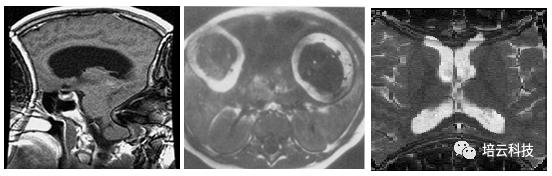

最后用三张经典的卷褶伪影临床图像作为结尾,对照着图像,回顾一下卷褶伪影的特点和原因。

图9 卷褶伪影:左, 出现在脑部矢状面频率编码方向; 中:出现在胸腹部横断位频率编码方向(两只手臂卷褶到腹部中);右, 出现在脑部横断位相位编码方向。